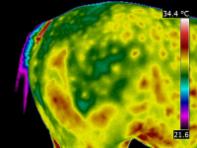

Equine Thermography will help you track changes over time; both prior to, during and post treatment. It provides a great tool in the recovery process, providing the veterinarian, farrier, therapy specialist or owner with a visual aid for monitoring the effectiveness of treatment and allowing changes to be made as the case progresses.

First I take an Initial Full Scan. This will show not only the extent of the known injury but also how the injury has impacted on the horses body as a whole. I then take periodic scans of the injury site to track the healing process.